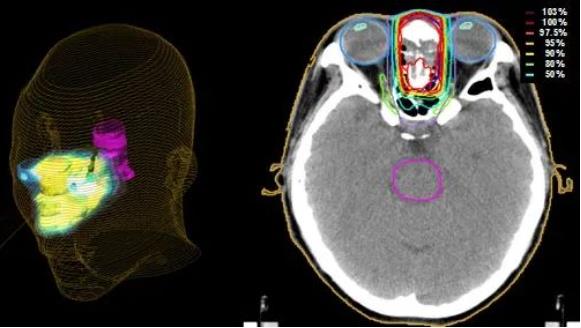

日本質子治療:頭頸癌

頭頸癌是指發生在面部和頸部的惡性腫瘤,是指從面部到頸部,大致是頭部下方到鎖骨區間,主要包括耳、鼻、鼻竇... -